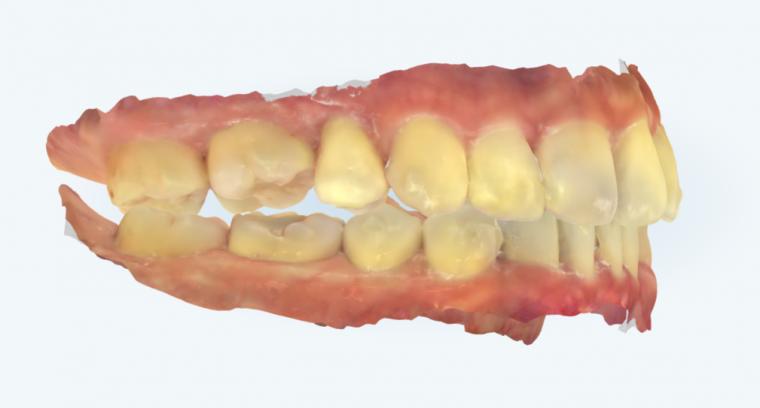

まず、アーチレングスディスクレパンシーです。

歯列弓の長さと歯の大きさの不調和を評価せずに、前歯の角度だけで抜歯を決めることはできません。

咬合面から見たときに、どの程度スペースが不足しているのか、あるいは本当に不足しているのかを確認することが前提になります。

次に、叢生量です。

叢生が強い症例では、そもそも歯が理想的に配列されません。

叢生の程度を無視した抜歯判断は、治療途中あるいは治療後に問題を生じやすくなります。